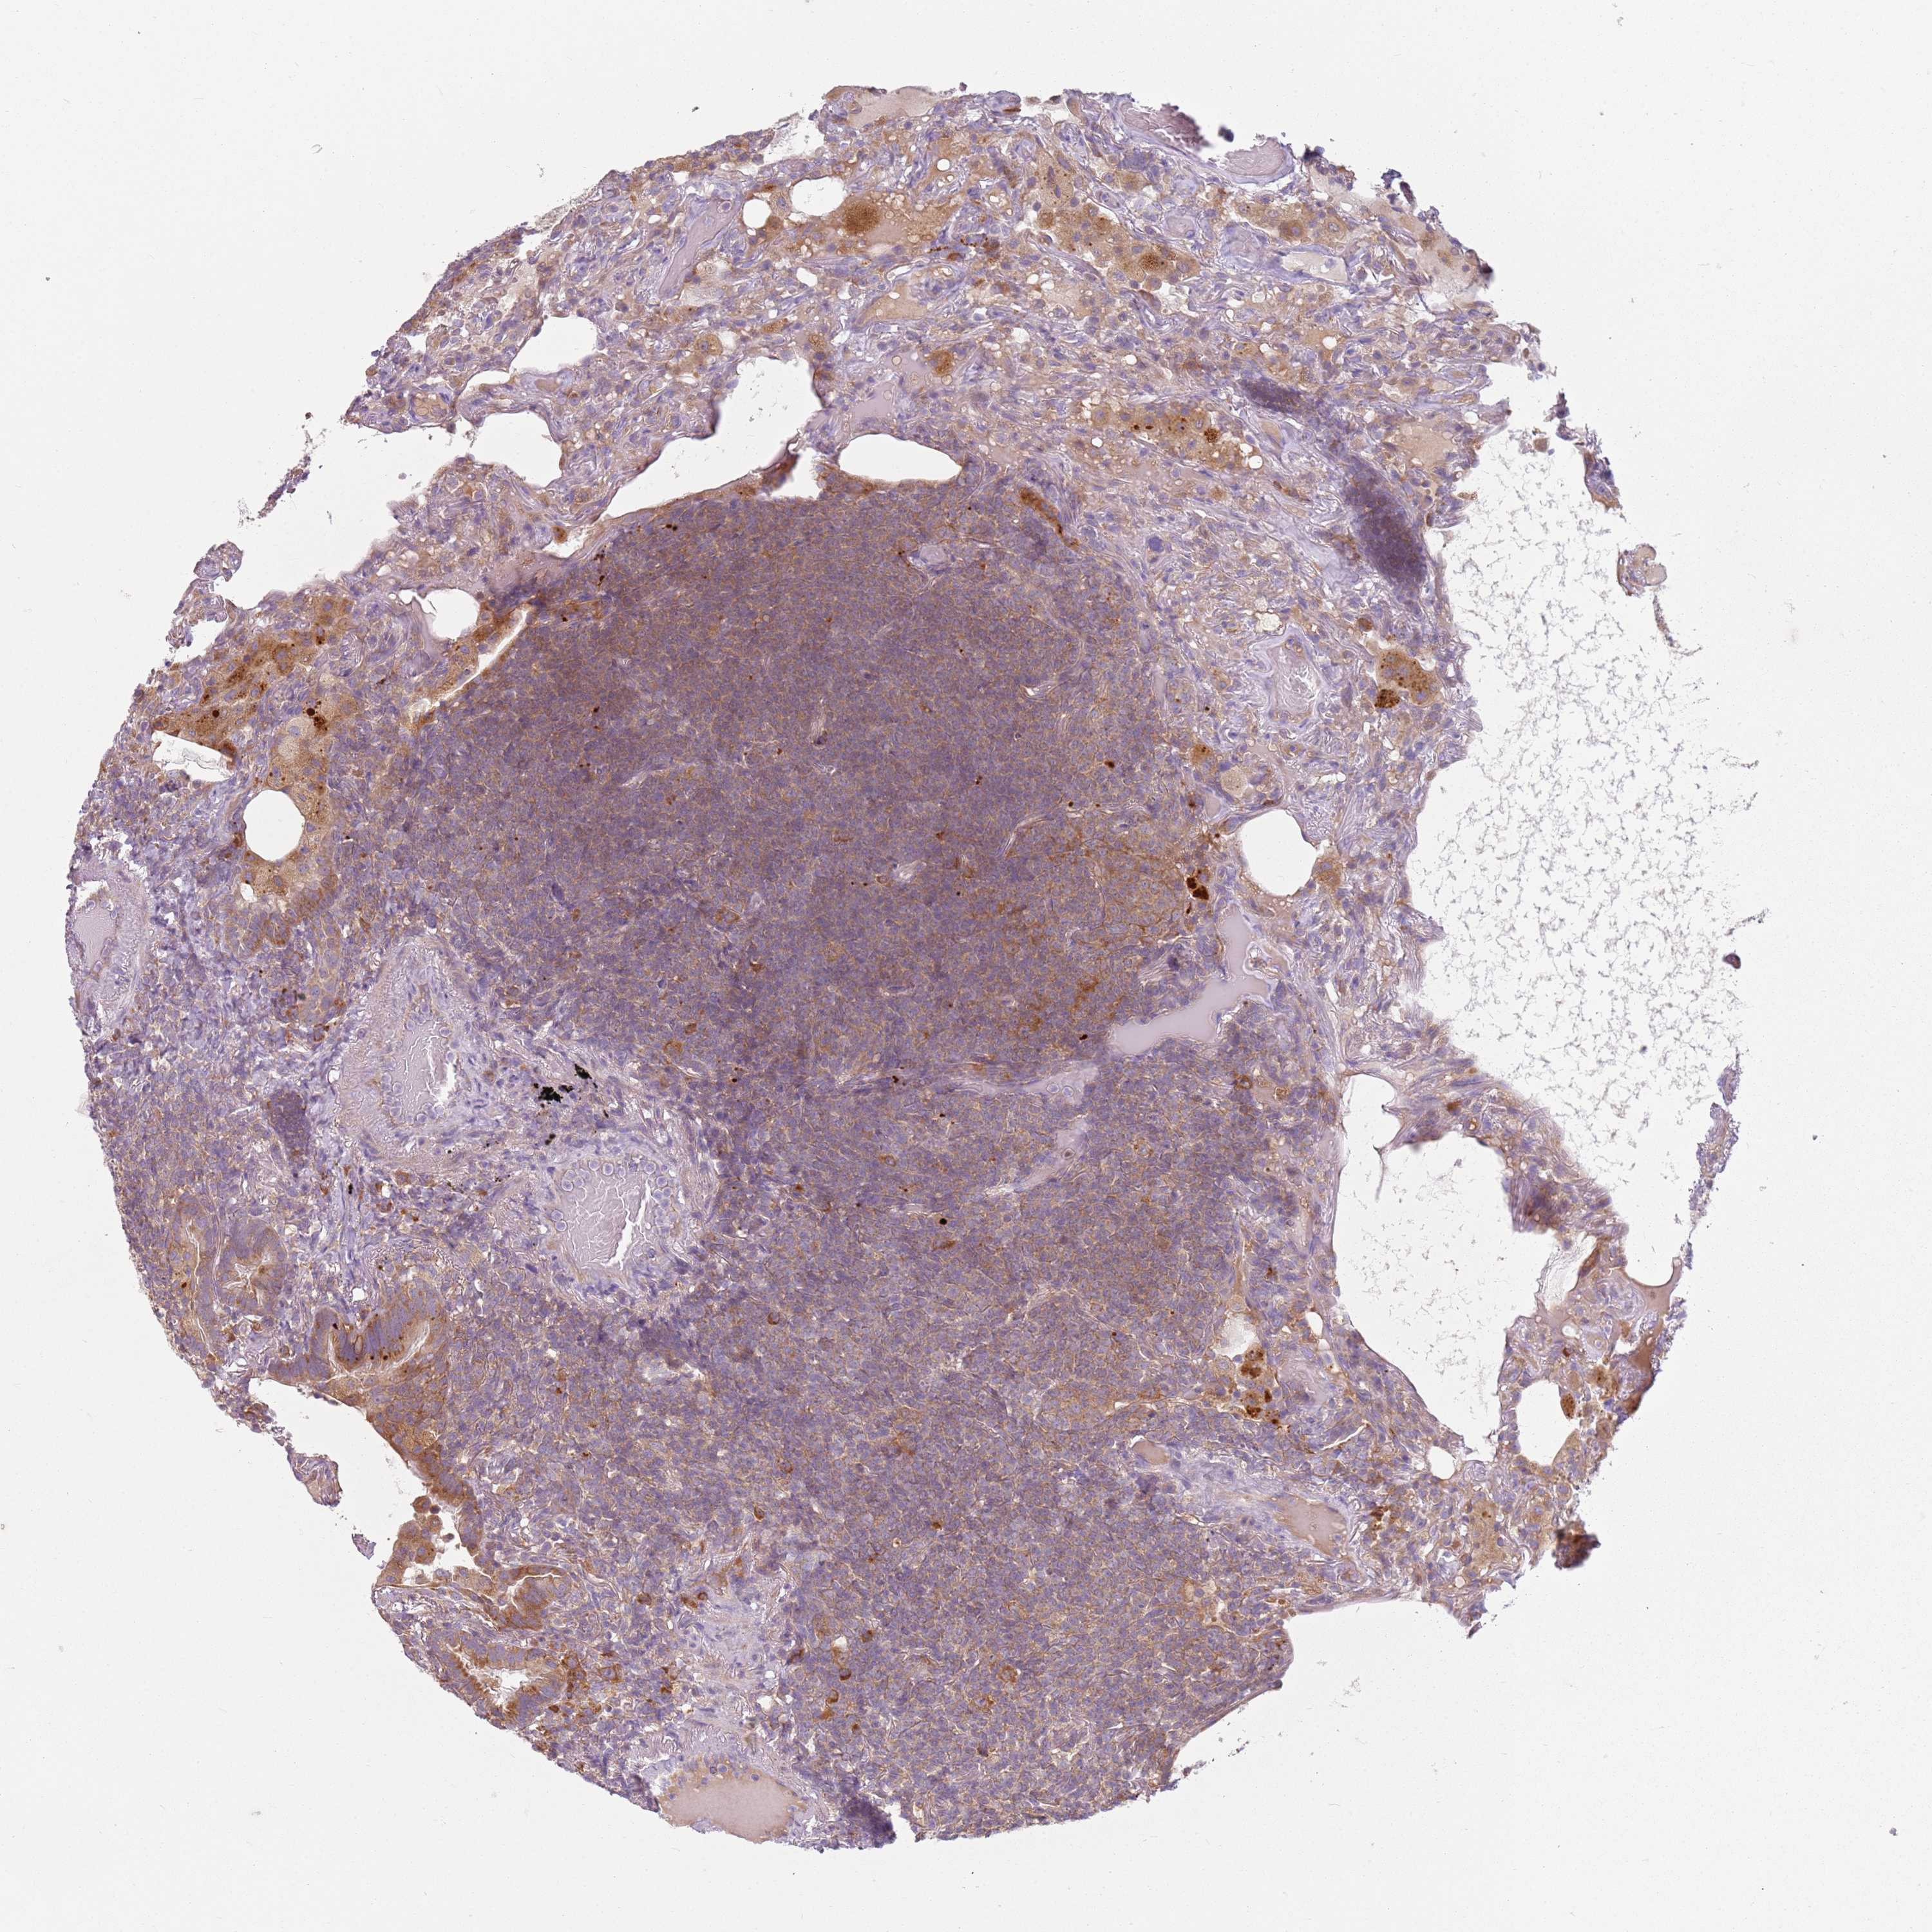

LYMPHOMA - Protein expressioni

A mouse-over function shows sample information and annotation data. Click on an image to view it in a full screen mode. Samples can be filtered based on level of antibody staining by selecting one or several of the following categories: high, medium, low and not detected. The assay and annotation is described here.

Antibody stainingi

Antibody staining in the annotated cell types in the current human tissue is reported as not detected, low, medium, or high, based on conventional immunohistochemistry profiling in selected tissues. This score is based on the combination of the staining intensity and fraction of stained cells.

Each image is clickable and will lead to virtual microscopy that enables deeper exploration of all samples and also displays staining intensity scores, fraction scores and subcellular localization as well as patient and tissue information for each sample.

Antibody HPA047132

Staining

High

Medium

Low

Not detected

Intensity

Strong

Moderate

Weak

Negative

Quantity

>75%

75%-25%

<25%

None

Location

Nuclear

Cytoplasmic/membranous

Cytoplasmic/membranous,nuclear

Hodgkin's disease, NOS

Malignant lymphoma, non-Hodgkin's type, High grade

Malignant lymphoma, non-Hodgkin's type, Low grade